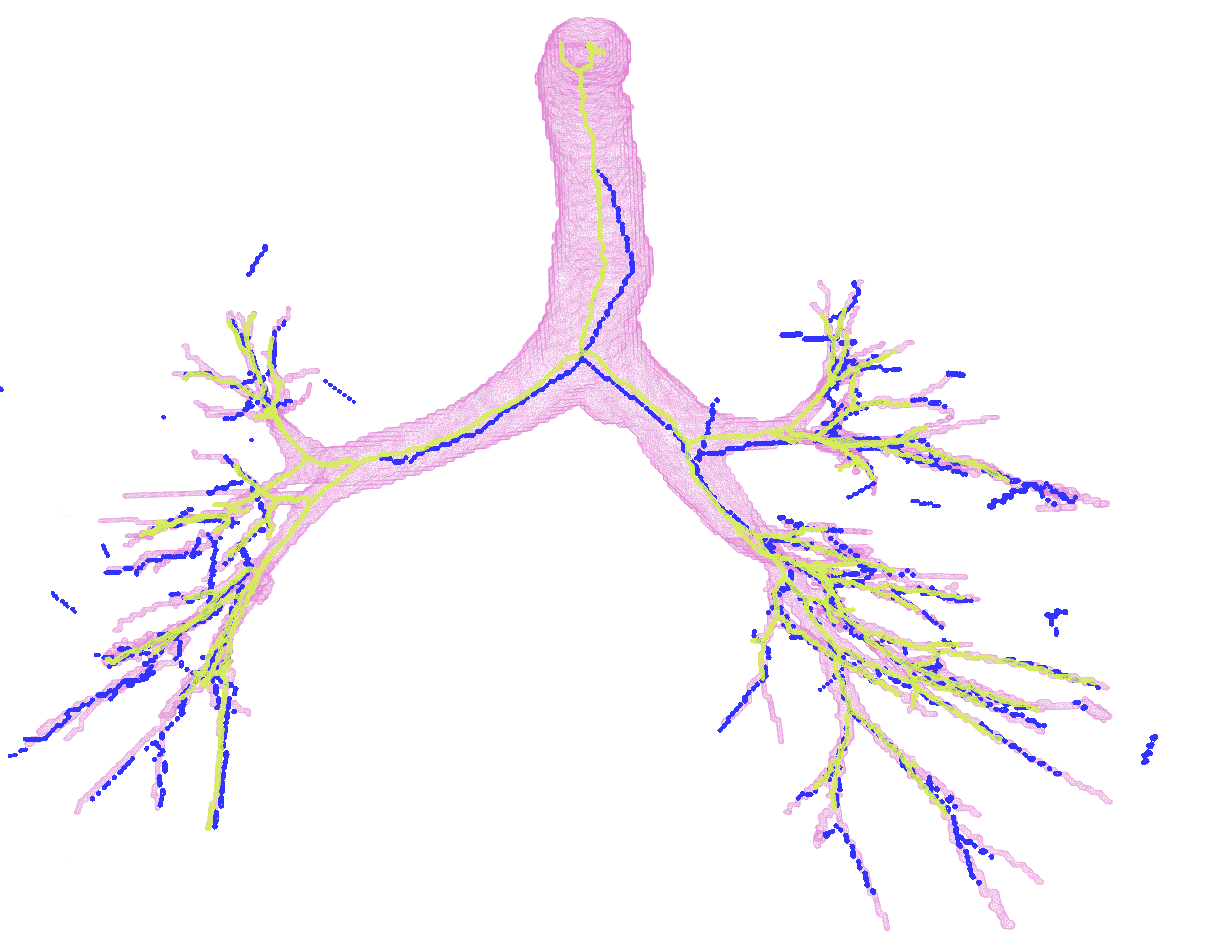

In Figure 2, first we present the predicted subgraph for one of the images. The gray dots are nodes of the over-complete graph with features, , extracted using Bayesian smoothing; the edges are colour-coded providing an insight into the performance of the method: yellow edges are true positives, red edges are false positives and blue edges are false negatives compared to the ground truth connectivity derived from the reference segmentations. Several of the false negatives are spaced closely, and in fact, do not contribute to the false negative error, , after generating the binary segmentations. The figure to the right in Figure 2 shows four predicted centerlines overlaid with the reference segmentation and centerlines from the voxel-classifier approach. Clearly, the MFN method is able to detect more branches as seen in most of the branch ends, which is also captured as the reduction in in Table 1. Some of the false positive predictions from MFN method appear to be a missing branch in the reference as seen in the first of the four scans. However, there are few other false positive predictions that could be due to the model using only pairwise potentials; this can be alleviated either by using higher order neighbourhood information or with basic post-processing. The centerlines extracted from MFN are slightly offset from the center of airways at larger scales; this could be due to the sparsity of the nodes at those scales and can be overcome by increasing resolution of the input graph.